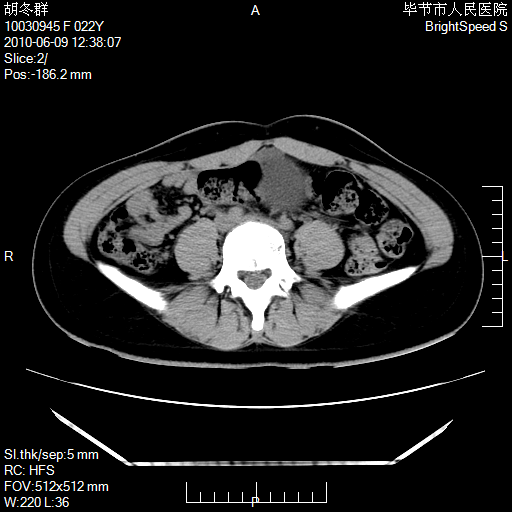

患者23岁,发现腹部包块3月。

盆腔内囊性占位;穿刺或者直接手术拿掉即可,不必紧张。

左侧卵巢囊腺瘤或囊腺癌

盆腔内囊性占位性病变;考虑左侧卵巢囊腺瘤。

有分隔、壁薄,支持考虑左侧卵巢囊腺瘤。

左侧卵巢浆液性囊腺瘤。

支持左侧附件区囊性占位,多考虑为囊腺瘤。

支持考虑左侧卵巢囊腺瘤;宫腔积液。

有分隔、壁薄,支持考虑左侧卵巢囊腺瘤。排尿后,膀胱缩小,由于重力作用,肿块下移就到了膀胱位置,很好理解。